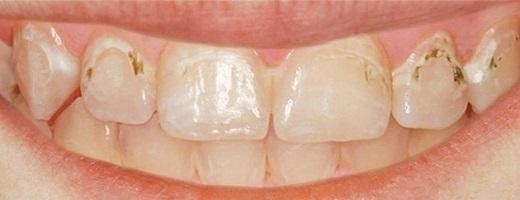

Признаки поверхностного кариеса.

<Нередко во время приема еды или употребления горячих (холодных) напитков человек чувствует некоторую болезненность зубов, которая быстро проходит. Считая ее незначительным признаком, или, принимая ее за индивидуальную реакцию зубов на раздражители, большинство не спешит обращаться к стоматологу. На самом же деле это и есть один из основных симптомов поверхностного кариеса.

Для поверхностного кариеса характерна слабовыраженная симптоматика. Дефект дентина незаметен при самостоятельном визуальном осмотре, а кратковременную болезненность, возникающую при контакте пораженного зуба с химическими или термическими раздражителями, больной воспринимает, как временное повышение чувствительности зубной эмали. Следует отметить, что при поверхностном кариесе боль проходит непосредственно после прекращения воздействия химического, механического или термического раздражителя.

Определить наличие поверхностного кариеса можно только при тщательном стоматологическом осмотре. При визуальном осмотре заболевание проявляется в виде участка деминерализованной эмали, которая имеет желто-серый цвет.

Поверхностный кариес — это начальная стадия разрушения зубной эмали, и многие люди не всегда осознают его серьезность. Этиология этого заболевания связана с воздействием бактерий, которые образуют налет и выделяют кислоты, разрушающие эмаль. Симптомы могут быть неочевидными: на начальных этапах кариес может проявляться лишь легким дискомфортом или изменением цвета зуба. Однако при отсутствии лечения он может прогрессировать, приводя к более серьезным проблемам.